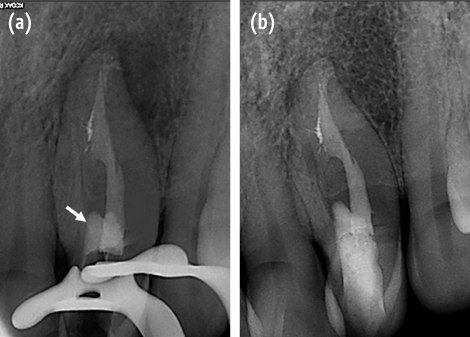

From the clinical and radiographic findings, we diagnosed chronic apical periodontitis of the maxillary left lateral incisor. The CBCT images revealed perforation and external root irregularity on the labial aspect (

Figure 2). A rubber dam was placed, and the tooth was prepared to provide adequate endodontic access. With the use of a microscope (OPMI pico Dental Microscope, Carl Zeiss, Oberkochen, Germany), 1 root canal and invagination were found.

Figure 2A set of transverse CBCT scan showing external concavity of the maxillary left lateral incisor. Note perforation communicates with periodontium through this concavity (white arrow). CBCT, cone-beam computed tomography.